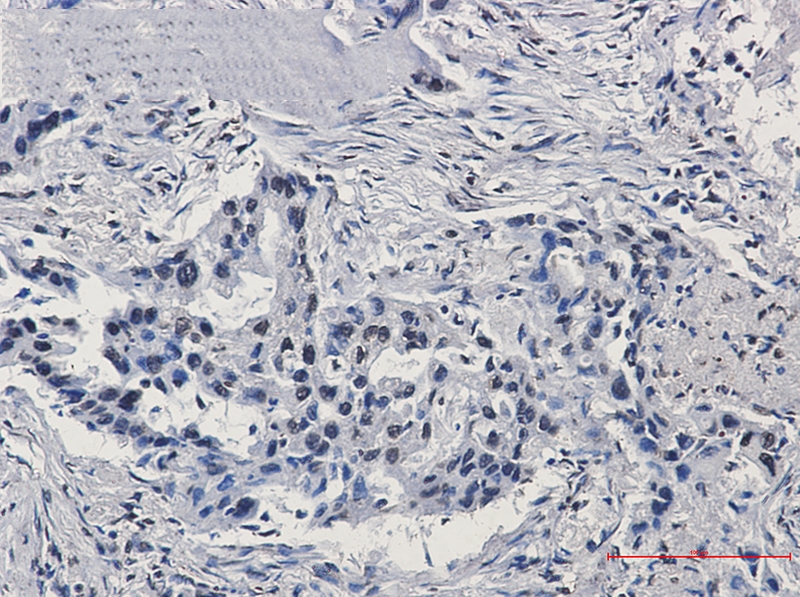

:使用 Anti-phospho-Akt (Ser473) Rabbit mAb 对石蜡包埋的人乳腺癌组织进行免疫组织化学分析。(图 A)使用免疫组化试剂盒M&R HRP/DAB Detection IHC Kit,抗体 1:100 稀释;(图 B) 采用普通免疫组化试剂盒,抗体 1:25 稀释。 图 6 免疫组化实验检测 Erk1/2 表达 注:使用 Anti-Erk1/2 Mouse mAb与p44/42 MAPK (Erk1/2)Rabbit mAb 对正常小鼠心脏组织进行免疫